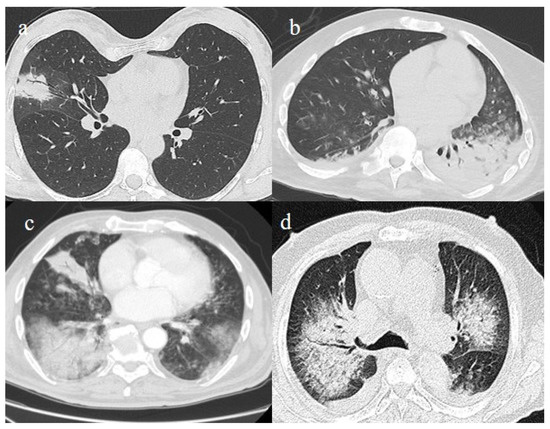

- Schultz, M.J.; van Meenen, D.M.; Bos, L.D. COVID-19-related acute respiratory distress syndrome: Lessons learned during the pandemic. Lancet Respir. Med. 2022, 10, 1108–1110. [Google Scholar] [CrossRef]

- Aslan, A.; Aslan, C.; Zolbanin, N.M.; Jafari, R. Acute respiratory distress syndrome in COVID-19: Possible mechanisms and therapeutic management. Pneumonia 2021, 13, 1–15. [Google Scholar] [CrossRef]

- Lu, S.; Huang, X.; Liu, R.; Lan, Y.; Lei, Y.; Zeng, F.; Tang, X.; He, H. Comparison of COVID-19 Induced Respiratory Failure and Typical ARDS: Similarities and Differences. Front. Med. 2022, 9, 829771. [Google Scholar] [CrossRef]

- Pfortmueller, C.A.; Spinetti, T.; Urman, R.D.; Luedi, M.M.; Schefold, J.C. COVID-19-associated acute respiratory distress syndrome (CARDS): Current knowledge on pathophysiology and ICU treatment—A narrative review. Best Pract. Res. Clin. Anaesthesiol. 2020, 35, 351–368. [Google Scholar] [CrossRef]

- Gosangi, B.; Rubinowitz, A.N.; Irugu, D.; Gange, C.; Bader, A.; Cortopassi, I. COVID-19 ARDS: A review of imaging features and overview of mechanical ventilation and its complications. Emerg. Radiol. 2022, 29, 23–34, Erratum in Emerg. Radiol. 2022, 29, 225. [Google Scholar] [CrossRef]

- Melhorn, J.; Achaiah, A.; Conway, F.M.; Thompson, E.M.; Skyllberg, E.W.; Durrant, J.; Hasan, N.A.; Madani, Y.; Naran, P.; Vijayakumar, B.; et al. Pneumomediastinum in COVID-19: A phenotype of severe COVID-19 pneumonitis? The results of the United Kingdom (POETIC) survey. Eur. Respir. J. 2022, 60, 2102522. [Google Scholar] [CrossRef]

- Khaire, N.; Deshmukh, S.; Agarwal, E.; Mahale, N.; Khaladkar, S.; Desai, S.; Kulkarni, A. “Pneumomediastinum: A marker of severity in COVID-19 disease”. Heliyon 2023, 9, e12981. [Google Scholar] [CrossRef] [PubMed]

- Tetaj, N.; Garotto, G.; Albarello, F.; Mastrobattista, A.; Maritti, M.; Stazi, G.V.; Marini, M.C.; Caravella, I.; Macchione, M.; De Angelis, G.; et al. Incidence of Pneumothorax and Pneumomediastinum in 497 COVID-19 Patients with Moderate–Severe ARDS over a Year of the Pandemic: An Observational Study in an Italian Third Level COVID-19 Hospital. J. Clin. Med. 2021, 10, 5608. [Google Scholar] [CrossRef] [PubMed]

- Kecskes, G.; Szabo, A.; Sutori, D.; Maroti, P.; Marovics, G.; Molnar, T.F. Pneumothorax/pneumomediastinum and pre-existing lung pathology in ventilated COVID-19 patients: A cohort study. J. Thorac. Dis. 2022, 14, 4733–4740. [Google Scholar] [CrossRef] [PubMed]

- Dubey, R.; Sen, K.K.; Mishra, A. Barotrauma and its complications in COVID-19 patients: A retrospective study at tertiary care hospital of Eastern India. Bull. Natl. Res. Cent. 2022, 46, 1–8. [Google Scholar] [CrossRef] [PubMed]

- Capaccione, K.M.; D’souza, B.; Leb, J.; Luk, L.; Duong, J.; Tsai, W.-Y.; Navot, B.; Dumeer, S.; Mohammed, A.; Salvatore, M.M. Pneumothorax rate in intubated patients with COVID-19. Acute Crit. Care 2021, 36, 81–84. [Google Scholar] [CrossRef]

- McGuinness, G.; Zhan, C.; Rosenberg, N.; Azour, L.; Wickstrom, M.; Mason, D.M.; Thomas, K.M.; Moore, W.H. IncreaIncidence of Barotrauma in Patients with COVID-19 on Invasive Mechanical Ventilation. Radiology 2020, 297, E252–E262. [Google Scholar] [CrossRef]

- Martinelli, A.W.; Ingle, T.; Newman, J.; Nadeem, I.; Jackson, K.; Lane, N.D.; Melhorn, J.; Davies, H.E.; Rostron, A.J.; Adeni, A.; et al. COVID-19 and pneumothorax: A multicentre retrospective case series. Eur. Respir. J. 2020, 56, 2002697. [Google Scholar] [CrossRef]

- Rodriguez-Arciniega, T.G.; Sierra-Diaz, E.; Flores-Martinez, J.A.; Alvizo-Perez, M.E.; Lopez-Leal, I.N.; Corona-Nakamura, A.L.; Castellanos-Garcia, H.E.; Bravo-Cuellar, A. Frequency and Risk Factors for Spontaneous Pneumomediastinum in COVID-19 Patients. Front. Med. 2021, 8, 662358. [Google Scholar] [CrossRef]

- Zantah, M.; Castillo, E.D.; Townsend, R.; Dikengil, F.; Criner, G.J. Pneumothorax in COVID-19 disease- incidence and clinical characteristics. Respir. Res. 2020, 21, 1–9. [Google Scholar] [CrossRef]

- Shahsavarinia, K.; Rahvar, G.; Soleimanpour, H.; Saadati, M.; Vahedi, L.; Mahmoodpoor, A. Spontaneous pneumomediastinum, pneumothorax and subcutaneous emphysema in critically ill COVID-19 patients: A systematic review. Pak. J. Med. Sci. 2022, 38, 730–735. [Google Scholar] [CrossRef]

- Hamouri, S.; AlQudah, M.; Albawaih, O.; Al-Zoubi, N.; Syaj, S. Spontaneous pneumothorax, pneumomediastinum and subcutaneous emphysema in non-ventilated COVID-19 patients. Futur. Sci. OA 2022, 8, FSO771. [Google Scholar] [CrossRef]

- Shaikh, N.; Al Ameri, G.; Shaheen, M.; Abdaljawad, W.I.; Al Wraidat, M.; Al Alawi, A.A.S.; Ali, H.S.; Mohamed, A.S.; Daeri, H.; Khatib, M.Y.; et al. Spontaneous pneumomediastinum and pneumothorax in COVID-19 patients: A tertiary care experience. Health Sci. Rep. 2021, 4, e339. [Google Scholar] [CrossRef]

- Gandolfo, C.; Bonfiglio, M.; Spinetto, G.; Ferraioli, G.; Barlascini, C.; Nicolini, A.; Solidoro, P. Pneumomediastinum associated with severe pneumonia related to COVID-19: Diagnosis and management. Minerva Medica 2022, 112, 779–785. [Google Scholar] [CrossRef]

- Espinosa, C.; Morente, L.M.; Mansour, E.H.; Yousefzadeh, M.L.; Muzaffarr, Z.M.; Salguero, D.; Vianna, S.D.; Quesada, L.D.; Poli, S.; Garcia, H. Predictors of Spontaneous Pneumomediastinum in Patients with COVID-19 and Ards on High-Flow Nasal Cannula. Chest 2022, 162, A1360–A1361. [Google Scholar] [CrossRef]

- Coppola, M.G.; Lugarà, M.; Tamburrini, S.; Madonna, P.; Panico, C.; Noschese, G.; Pone, E. Pneumomediastinum and Pneumothorax as Relevant Complications of Sub-Intensive Care of Patients with COVID-19: Description of a Case Series. Medicina 2021, 57, 919. [Google Scholar] [CrossRef]

- Palumbo, D.; Campochiaro, C.; Belletti, A.; Marinosci, A.; Dagna, L.; Zangrillo, A.; De Cobelli, F. Pneumothorax/pneumomediastinum in non-intubated COVID-19 patients: Differences between first and second Italian pandemic wave. Eur. J. Intern. Med. 2021, 88, 144–146. [Google Scholar] [CrossRef]

- Xiang, T.; Fang, J.; Cheng, T.; Li, Z.; Wu, D.; Zhang, S.; Ge, S.; Zhang, W. Case report: Severe pneumonia and pneumomediastinum in a previously robust adolescent caused by Omicron BA.5.2. Front. Med. 2023, 10, e1132630. [Google Scholar] [CrossRef]

- Kanne, J.P.; Little, B.P.; Schulte, J.J.; Haramati, A.; Haramati, L.B. Long-term Lung Abnormalities Associated with COVID-19 Pneumonia. Radiology 2023, 306, e221806. [Google Scholar] [CrossRef]

- Han, X.; Fan, Y.; Alwalid, O.; Zhang, X.; Jia, X.; Zheng, Y.; Shi, H. Fibrotic Interstitial Lung Abnormalities at 1-year Follow-up CT after Severe COVID-19. Radiology 2021, 301, E438–E440. [Google Scholar] [CrossRef]

- Watanabe, A.; So, M.; Iwagami, M.; Fukunaga, K.; Takagi, H.; Kabata, H.; Kuno, T. One-year follow-up CT findings in COVID-19 patients: A systematic review and meta-analysis. Respirology 2022, 27, 605–616. [Google Scholar] [CrossRef]

- Bocchino, M.; Lieto, R.; Romano, F.; Sica, G.; Bocchini, G.; Muto, E.; Capitelli, L.; Sequino, D.; Valente, T.; Fiorentino, G.; et al. Chest CT–based Assessment of 1-year Outcomes after Moderate COVID-19 Pneumonia. Radiology 2022, 305, 479–485. [Google Scholar] [CrossRef] [PubMed]

- Cocconcelli, E.; Bernardinello, N.; Giraudo, C.; Castelli, G.; Giorgino, A.; Leoni, D.; Petrarulo, S.; Ferrari, A.; Saetta, M.; Cattelan, A.; et al. Characteristics and Prognostic Factors of Pulmonary Fibrosis After COVID-19 Pneumonia. Front. Med. 2022, 8, 823600. [Google Scholar] [CrossRef] [PubMed]